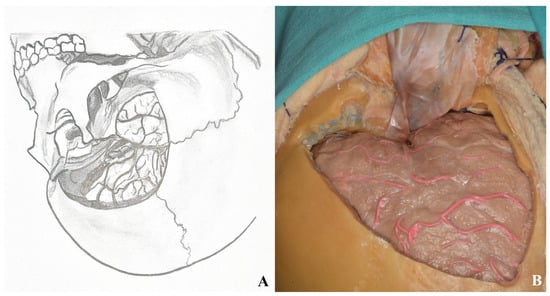

3.2.6. Dura Incision and Sylvian Fissure Opening

3.3. Lamina Terminalis

3.4. Lamina Terminalis Cistern